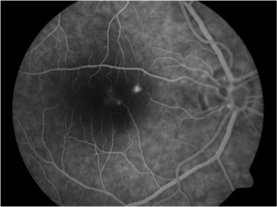

A 37-year-old woman (gravida 2, para 1, abortus 0), following an uncomplicated pregnancy except for a history of insulin-dependent gestational diabetes with good glycaemic control and a local Varicella-Zoster infection which treated successfully, underwent elective caesarean section under spinal anaesthesia with bupivacaine hydrochloride (10mg). Surgery was uneventful and two healthy twin-girls were delivered. Corticosteroids were at no point given. Antibiotics were given intraoperatively. Four days after the caesarean section the patient experienced a sudden decrease of visual acuity combined with a central scotoma and metamorphopsia in her right eye. At presentation, best-corrected visual acuity of the right eye was 8/20 with metamorphopsia, a central scotoma in Amsler's grid and blurred vision. Funduscopy of the right eye revealed a serous elevation of the macula (Figure 1 (A−C)). Fluorescein angiography (FA) disclosed three expanding points of fluorescein leakage at the foveolar avascular zone. Optical coherence tomography (OCT) sections through the macula showed a neurosensory retinal detachment with an increase in retinal thickness equal to 558μm.

Figure 1b FA displays an acute central serous chorioretinopathy with multifocal RPE hyper-fluorescence with a cluster of point of leakage (“expanding pinpoint”).